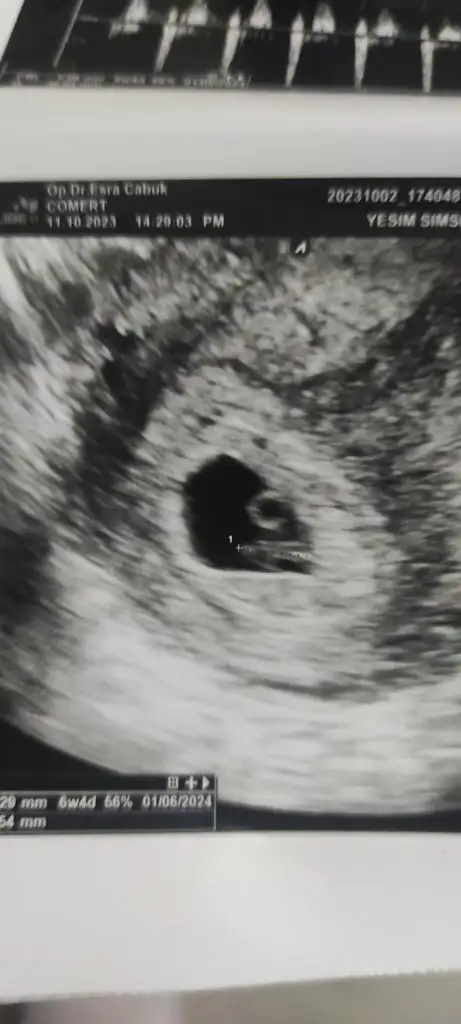

Ya benim içinde tahmin yapar mısınız? İlk resim 12 hafta ikinci ve üçüncü 6 hafta iken son fotoğrafta 14 hafta. Sizce cinsiyeti ne belli oluyor mu?